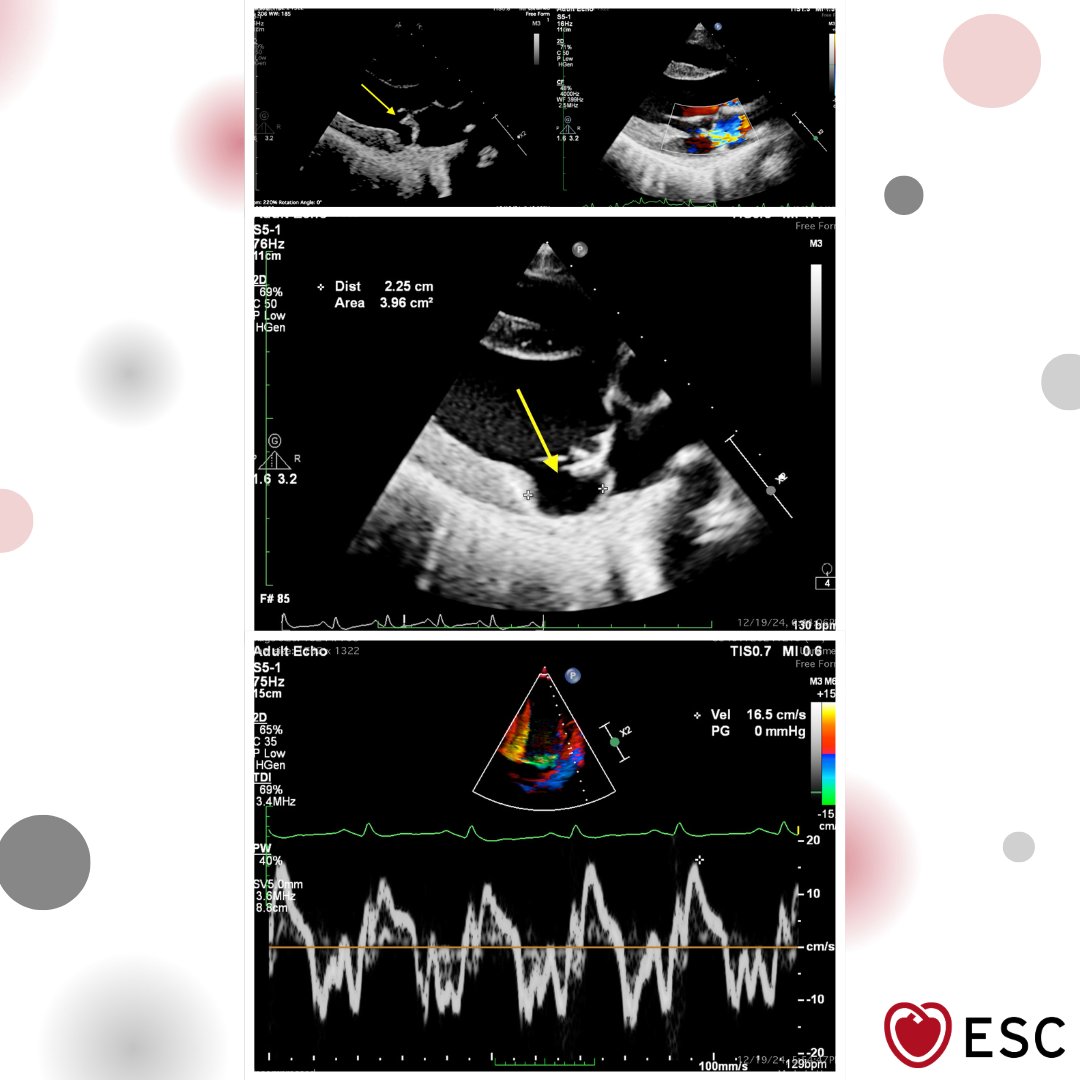

#ImageOfTheWeek by Avishkar Agrawal, Sumit Kumar, and Souvik Sardar from All India Institute of Medical Sciences, New Delhi, India A 28-year-old woman with mitral valve prolapse. What additional high-risk echo finding may be present? ow.ly/V7iS50YJNIU